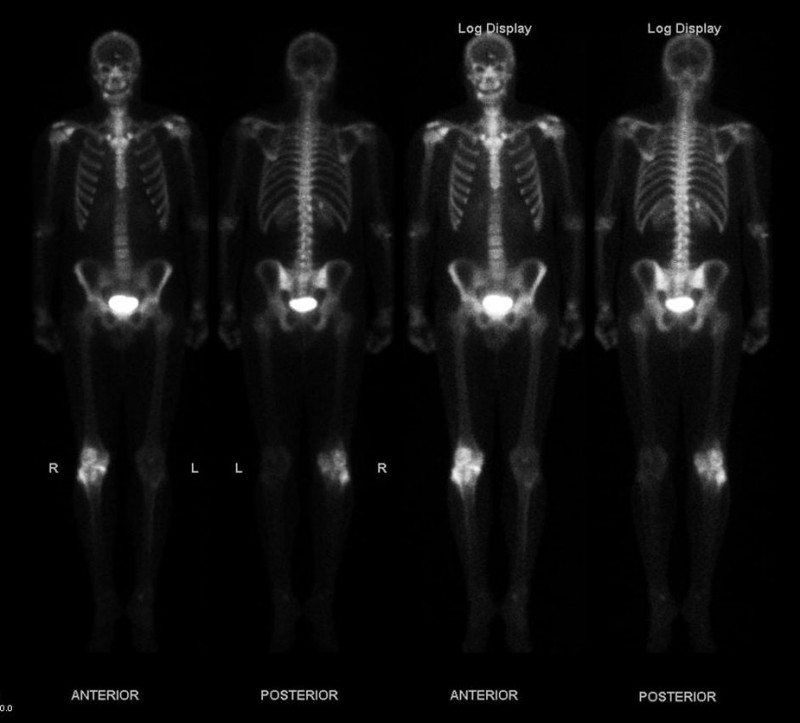

Gamma rays have a much greater range than either \(\alpha \)s or \(\beta \)s. In fact, if a given thickness of material, like a lead brick, absorbs 90% of the \(\gamma \)s, then a second lead brick will only absorb 90% of what got through the first. Thus, \(\gamma \)s do not have a well-defined range; we can only cut down the amount that gets through. Typically, \(\gamma \)s can penetrate many meters of air, go right through our bodies, and are effectively shielded (that is, reduced in intensity to acceptable levels) by many centimeters of lead. One benefit of \(\gamma \)s is that they can be used as radioactive tracers (see this figure).